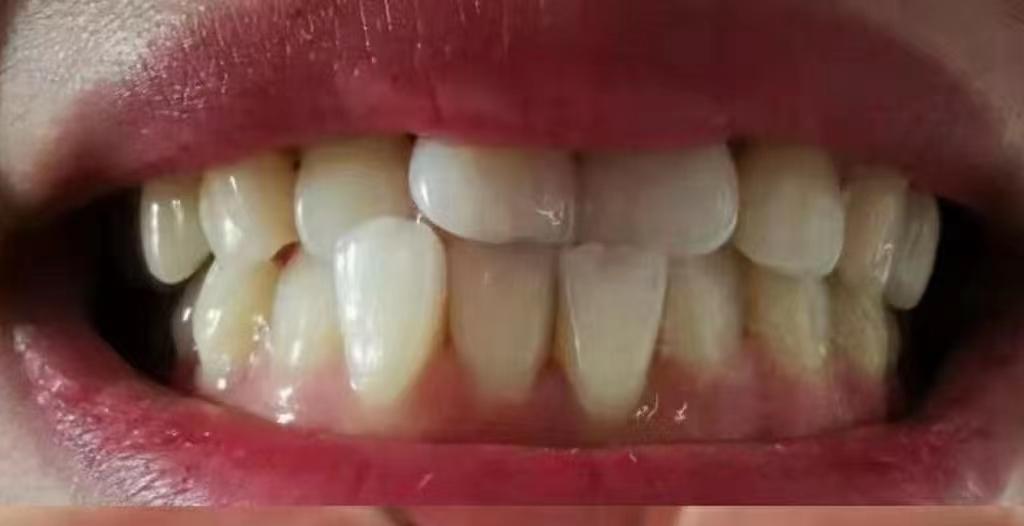

平時我們看到的自己牙齒可能這樣

看起來好像也還行

但你從牙醫(yī)視角看過自己的牙嗎!

就這兩顆自由飛翔的大門牙~能不影響咱的顏值嗎